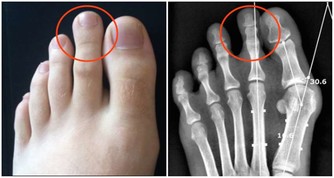

莧菜能平衡酸鹼,你的尿酸痛風就會好。

莧菜補血,就是紅莧菜,又使痛風消,

所以每天用一碗面線、一把莧菜,保證不會體重增加,保證尿酸痛風全部消掉。